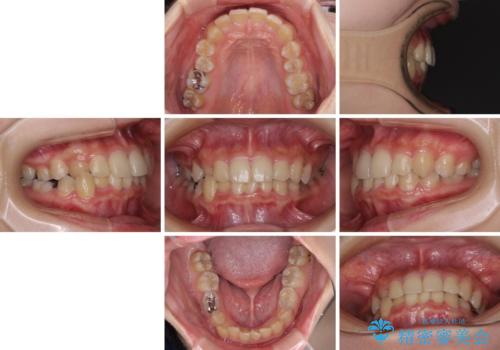

- 犬歯のクロスバイトを気にして来院された患者様です。

マウスピース矯正とワイヤー矯正の両方を提案しましたが、インビザラインの自己管理が煩わしいとのことで、ワイヤー装置による矯正治療を行うこととしました。

犬歯は歯根が太くて長いため、クロスバイトを改善するのは大変であることが多いですが、比較的スムーズに改善することができました。

インビザラインであったら、もっと期間はかかっていたような印象です。